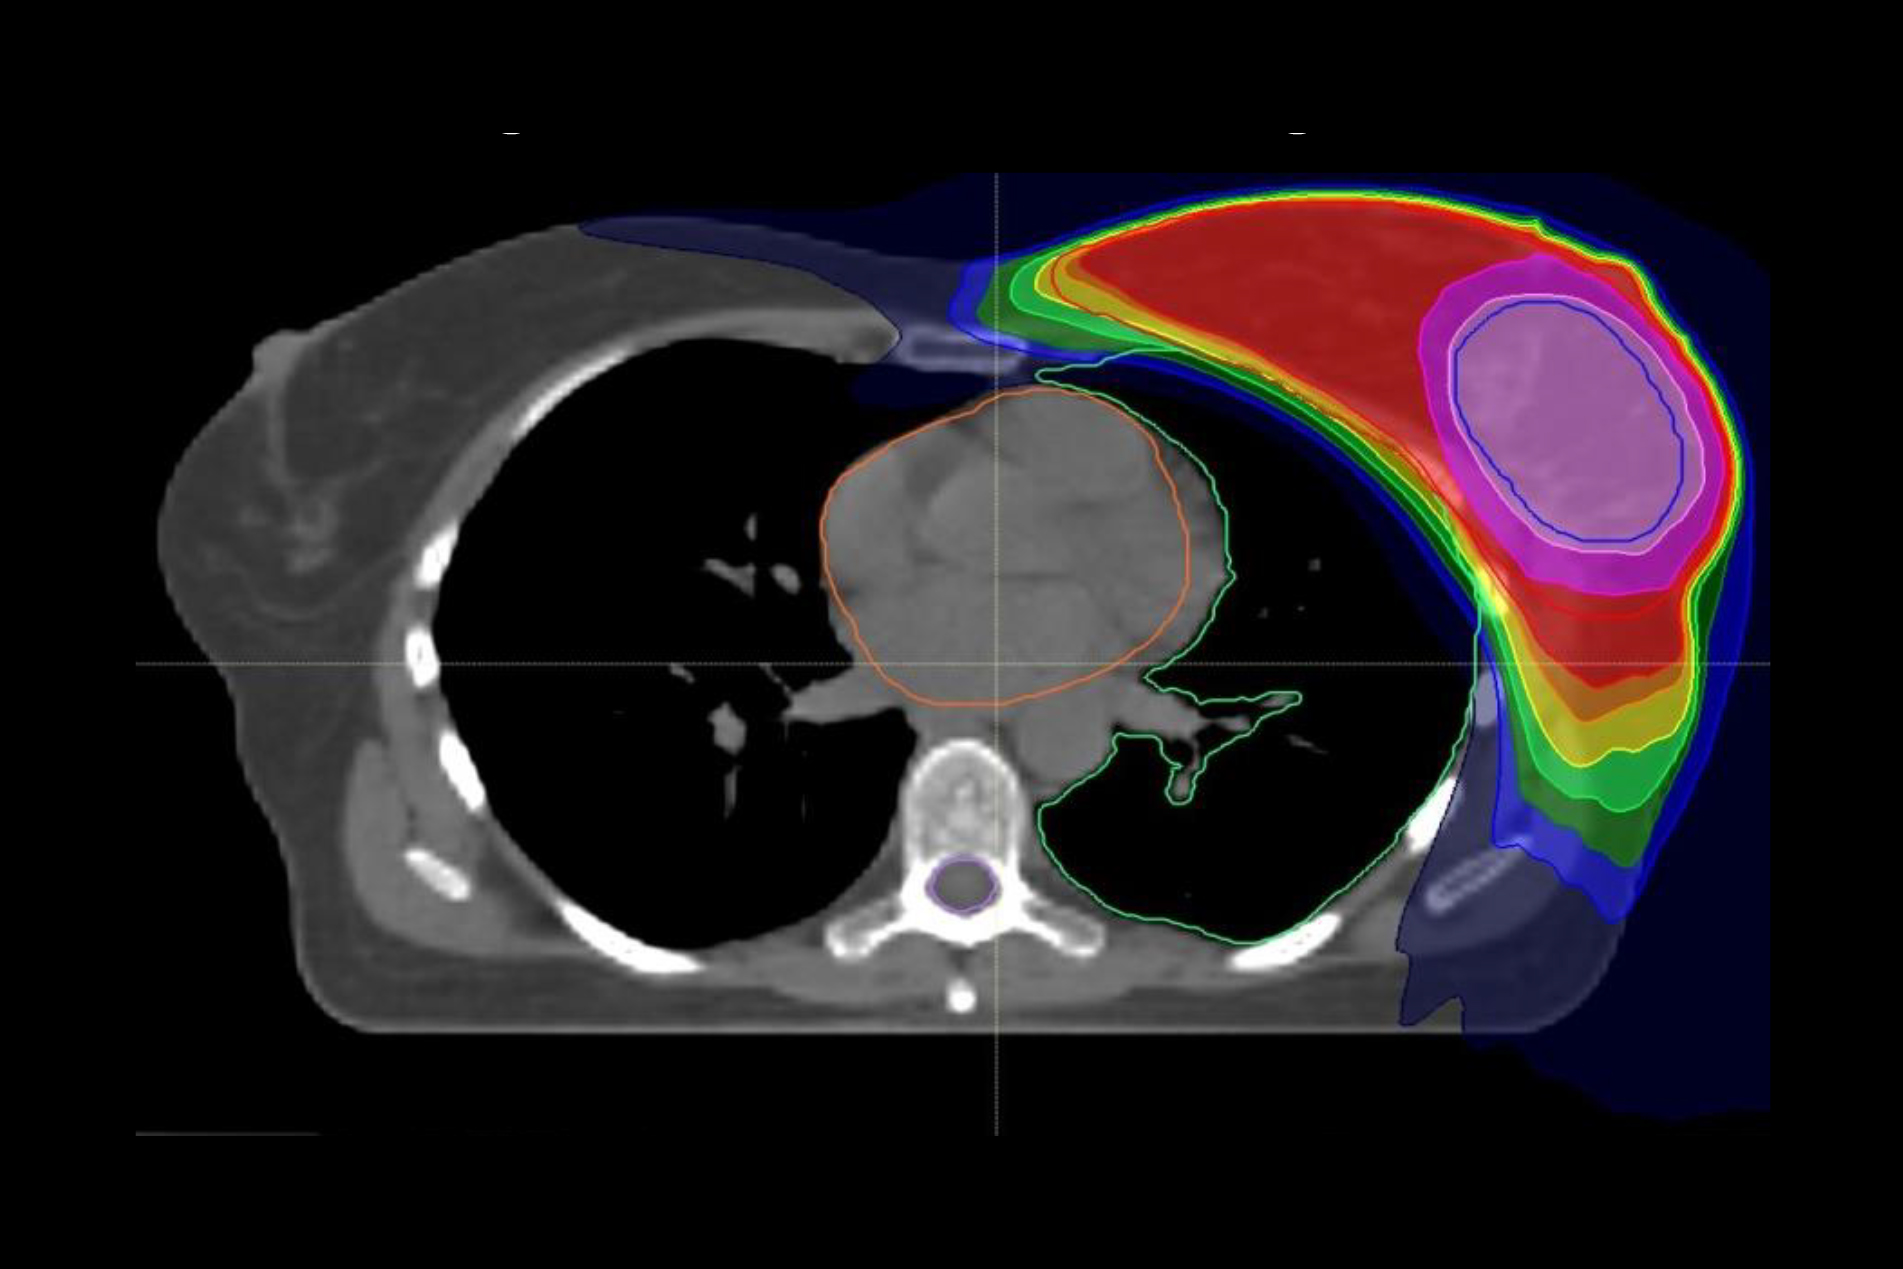

Nach der Brustkrebs-OP wird in der Regel zusätzlich zur Bestrahlung der gesamten Brust die unmittelbare Umgebung des entfernten Tumors gesondert intensiv bestrahlt. Diese „Boost“-Bestrahlung muss allerdings nicht zwangsläufig – wie bisher empfohlen – im Anschluss an die mehrwöchige Bestrahlung stattfinden. Sie ist ebenso wirksam, wenn sie simultan in ein modernes Bestrahlungskonzept integriert wird, wie eine im International Journal of Radiation Oncolocy • Biology • Physics veröffentlichte Studie unter Leitung der Radiologischen Universitätsklinik Heidelberg ergeben hat. Durch die integrierte Boost-Bestrahlung verkürzt sich die Strahlentherapie um rund 10 Tage auf fünf Wochen. Während der Nachbeobachtungszeit von fünf Jahren war das neue Bestrahlungskonzept in Behandlungs- und kosmetischem Ergebnis der Standartbehandlung gleichwertig. „Die kürzere Bestrahlungszeit ist für die Patientinnen eine deutliche Erleichterung und damit im Hinblick auf die Lebensqualität im Vorteil“, sagt Erstautorin Privatdozentin Dr. Juliane Hörner-Rieber, Geschäftsführende Oberärztin der Abteilung Radioonkologie und Strahlentherapie an der Radiologischen Universitätsklinik Heidelberg.

Die aktuellen Leitlinien der Amerikanischen Gesellschaft für Radioonkologie (ASTRO) zur Strahlentherapie bei Brustkrebs empfehlen bislang noch die anschließende Boost-Bestrahlung. „Das liegt daran, dass es bisher noch keine belastbaren Daten zur Bewertung des integrierten Boosts gab“, so Professor Dr. Dr. Jürgen Debus, Ärztlicher Direktor der Radiologischen Universitätsklinik und Letztautor der Studie. „Unsere Ergebnisse sind ein erster wichtiger Schritt zur evidenzbasierten Aktualisierung der Leitlinien.“ Insbesondere moderne Bestrahlungstechniken wie die sogenannte Intensitätsmodulierte Radiotherapie (IMRT), bei der Risikoorgane bestmöglich geschont werden können, haben der neuen Entwicklung den Weg geebnet. Inwieweit sich die Ergebnisse auf die seit rund drei Jahren zunehmend angewandte, verkürzte Radiotherapie der Brust übertragen lassen, ist Gegenstand aktueller Studien.